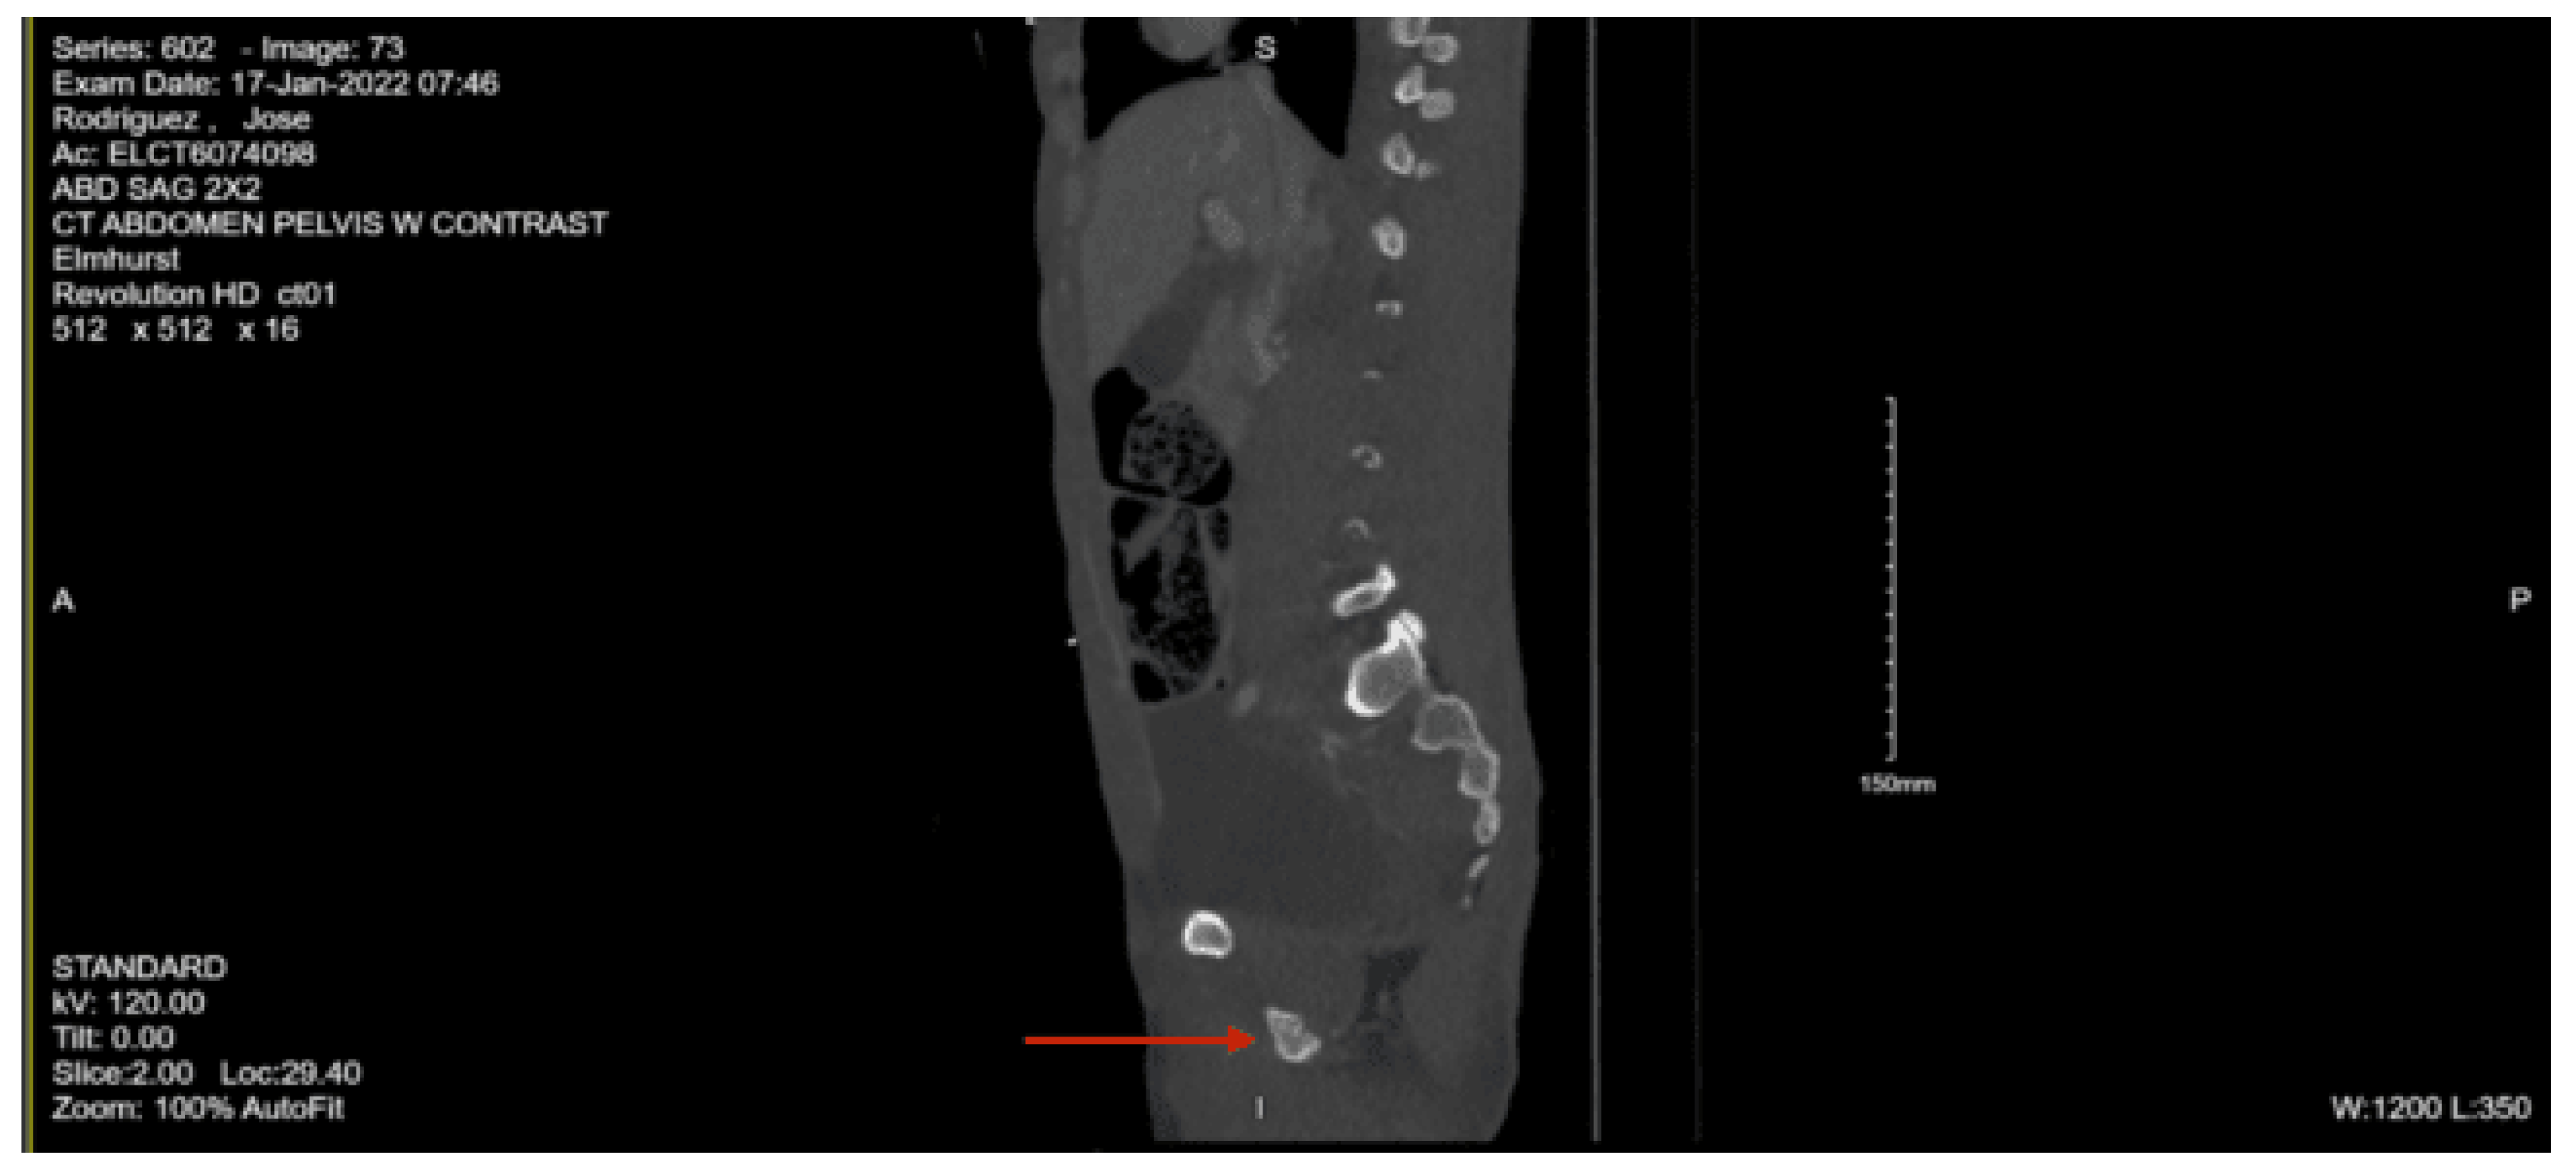

CT abdomen pelvis with contrast: There is retroperitoneal fluid surrounding the upper abdominal aorta without contrast blush. Linear flap within the upper abdominal aorta at the level of the celiac and SMA origins, concerning for traumatic injury. Lower thoracic findings include multiple posterolateral right rib fractures. Grade II hepatic injury. Periportal edema. Acute right L1 through L5 transverse process fractures. Acute right sacral ala fracture. Nondisplaced acute right inferior pubic ramus fracture. Nondisplaced acute fracture involving the lateral aspect of the right acetabulum.

Since the patient was found to have pneumothoraces and hemothorax, a right chest tube was inserted by the ED staff and connected to suction. Given the finding of suspected aortic injury from the CT abdomen pelvis with contrast, a CT angiography of the abdomen pelvis was performed, which showed no evidence of vascular abnormality. Pre-contrast imaging demonstrated a heterogeneous enhancement with persistent spotty nephrogram involving areas of the right kidney, which raised a concern for a renal contusion. The patient was admitted to the STICU for continued management of his traumatic injuries. Neurosurgery was consulted for the lumbar spine fractures and the sacral ala fracture. They recommended no acute surgical interventions and advocated for optimal pain control. Orthopedic surgery was consulted for the right sacral ala fracture and the lateral right acetabulum fracture, and recommended no orthopedic intervention at the time and no weight-bearing activity status. Psychiatry was consulted, given his history of psychiatric disease, and they recommended a two-to-one level of observation for unpredictable behavior, holding his standing home medications, and gave recommendations for agitation management.